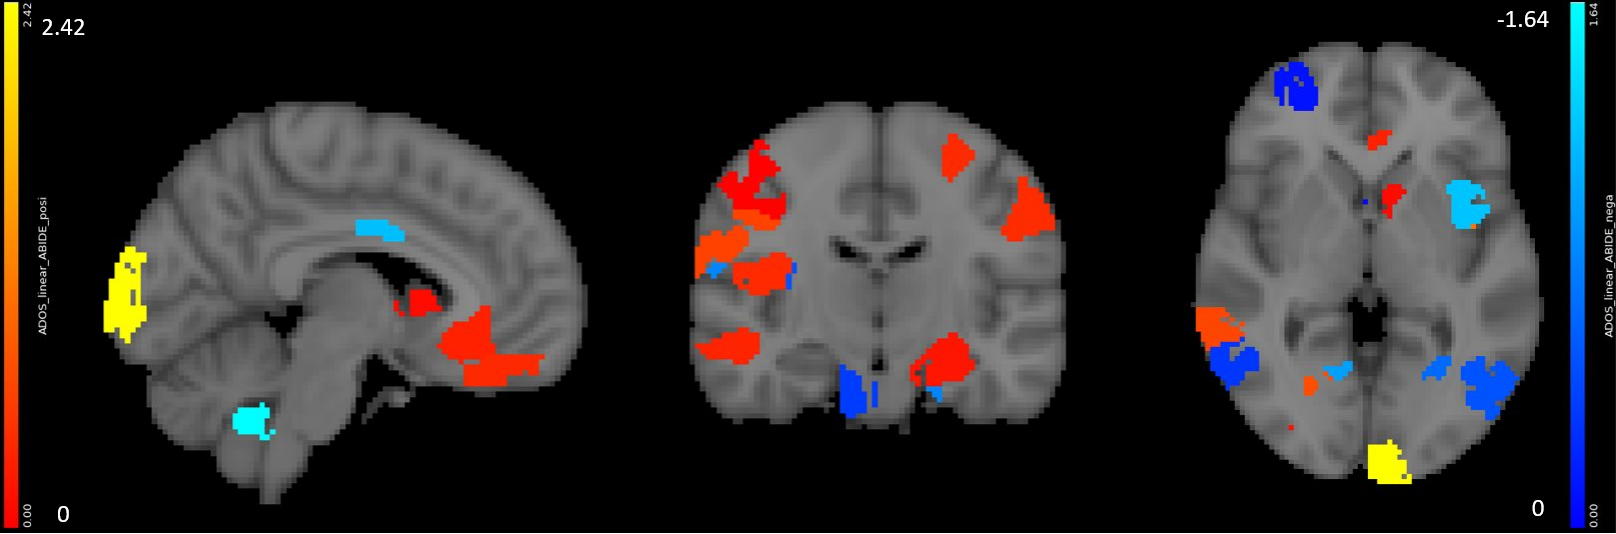

We performed similar experiments on the ABIDE dataset [15] using the UM and USM sites with five-fold cross validation. We selected male subjects diagnosed with ASD, resulting in 51 patients from UM and 13 patients from USM. We built models to predict the ADOS Gotham total score from voxel-mirrored homotopic connectivity images [16]. We set parameters the same as in section 3.1. Results are shown in Fig. 10.

For raw ADOS score, Björnsdotter et al. found no significant correlation with brain responses in fMRI scan [18]. Predictive models based on structural MRI achieved correlation of r=0.362 between predictions and measurements [19]. In our experiment with resting-state fMRI, we achieved correlation r=0.40 (Fig. 10).

Neurosynth decoder results (Fig. 9(d), Fig. 10 right figure) show that selected regions match the literature [11]. The selected regions are slightly different across experiments due to different tasks, datasets and target measures. Many regions are shared across experiments, such as prefrontal cortex and visual cortex.